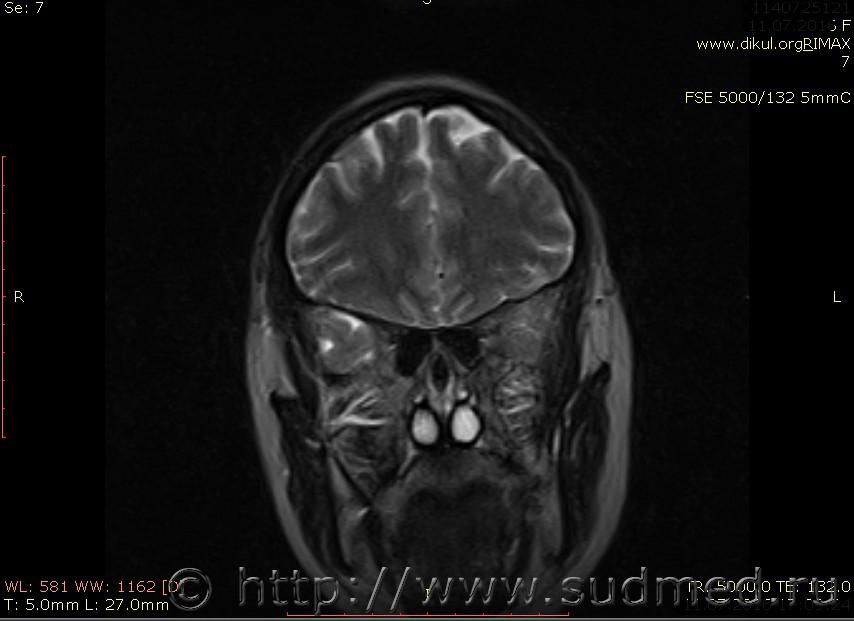

МРТ головного мозга показало: МР-данных за наличие очаговых изменений в веществе головного мозга на момент исследования не выявлено. МР-признаки нарушения соотношения в атланто-осевом суставе. Определяется ассиметрия положения зубовидного отростка С2 относительно боковых масс С1(справа 6,5; слева 4 мм.)

Сама по себе эта информация даёт основания подозревать вывих первого шейного позвонка, но однозначно не свидетельствует о наличии вывиха. Нужно смотреть на снимках наличие реакции со стороны мягких тканей, в т.ч. связочного аппарата, нужно анализировать особенности неврологической патологии, её динамику и проч.

Запрошен электронный вариант снимков из учреждения, где делалось МРТ. Т.к. с самого снимка делать копии не получается,очень мелкие кадры. Завтра попробую вставить в сообщение. (Но СМЭ снимок не смотрел, смотрел только мед.карту, в которой находилось описание МРТ).

Посмотрите пожалуйста снимки, надеюсь на них видны позвонки С1,С2?

Прошу прощения, попробую снова прикрепить файлы. Данные учреждения и пациента убраны.